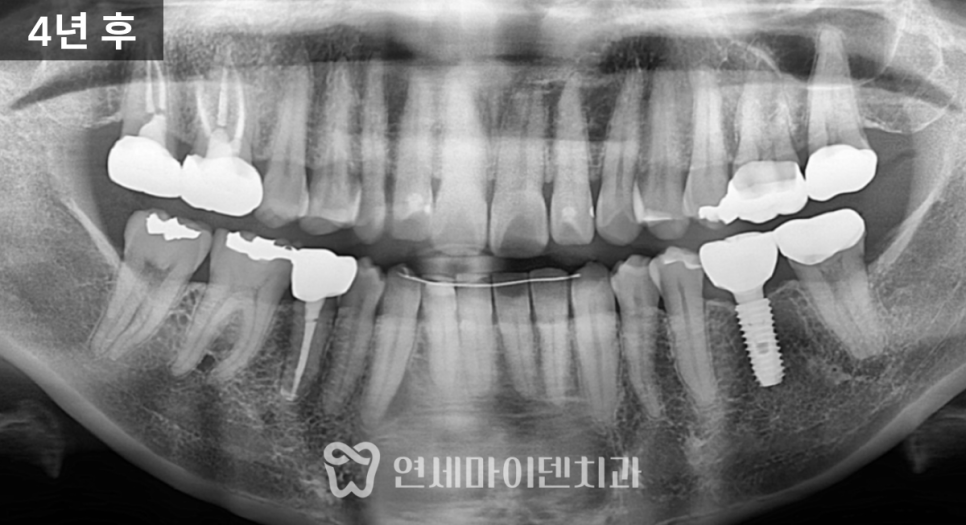

오랜 기간 방치하면서 뼈가 많이 녹아 있었고,

반대편 치아도 비슷한 문제로 발치한 상태였습니다.

몇 달 뒤에는 뼈가 다시 차오르면서

치아를 정상적으로 사용할 수 있었습니다.

발치 직전까지 갔던 치아는

재신경치료 후 지르코니아 보철로 완성되어

현재까지도 잘 사용되고 있습니다.